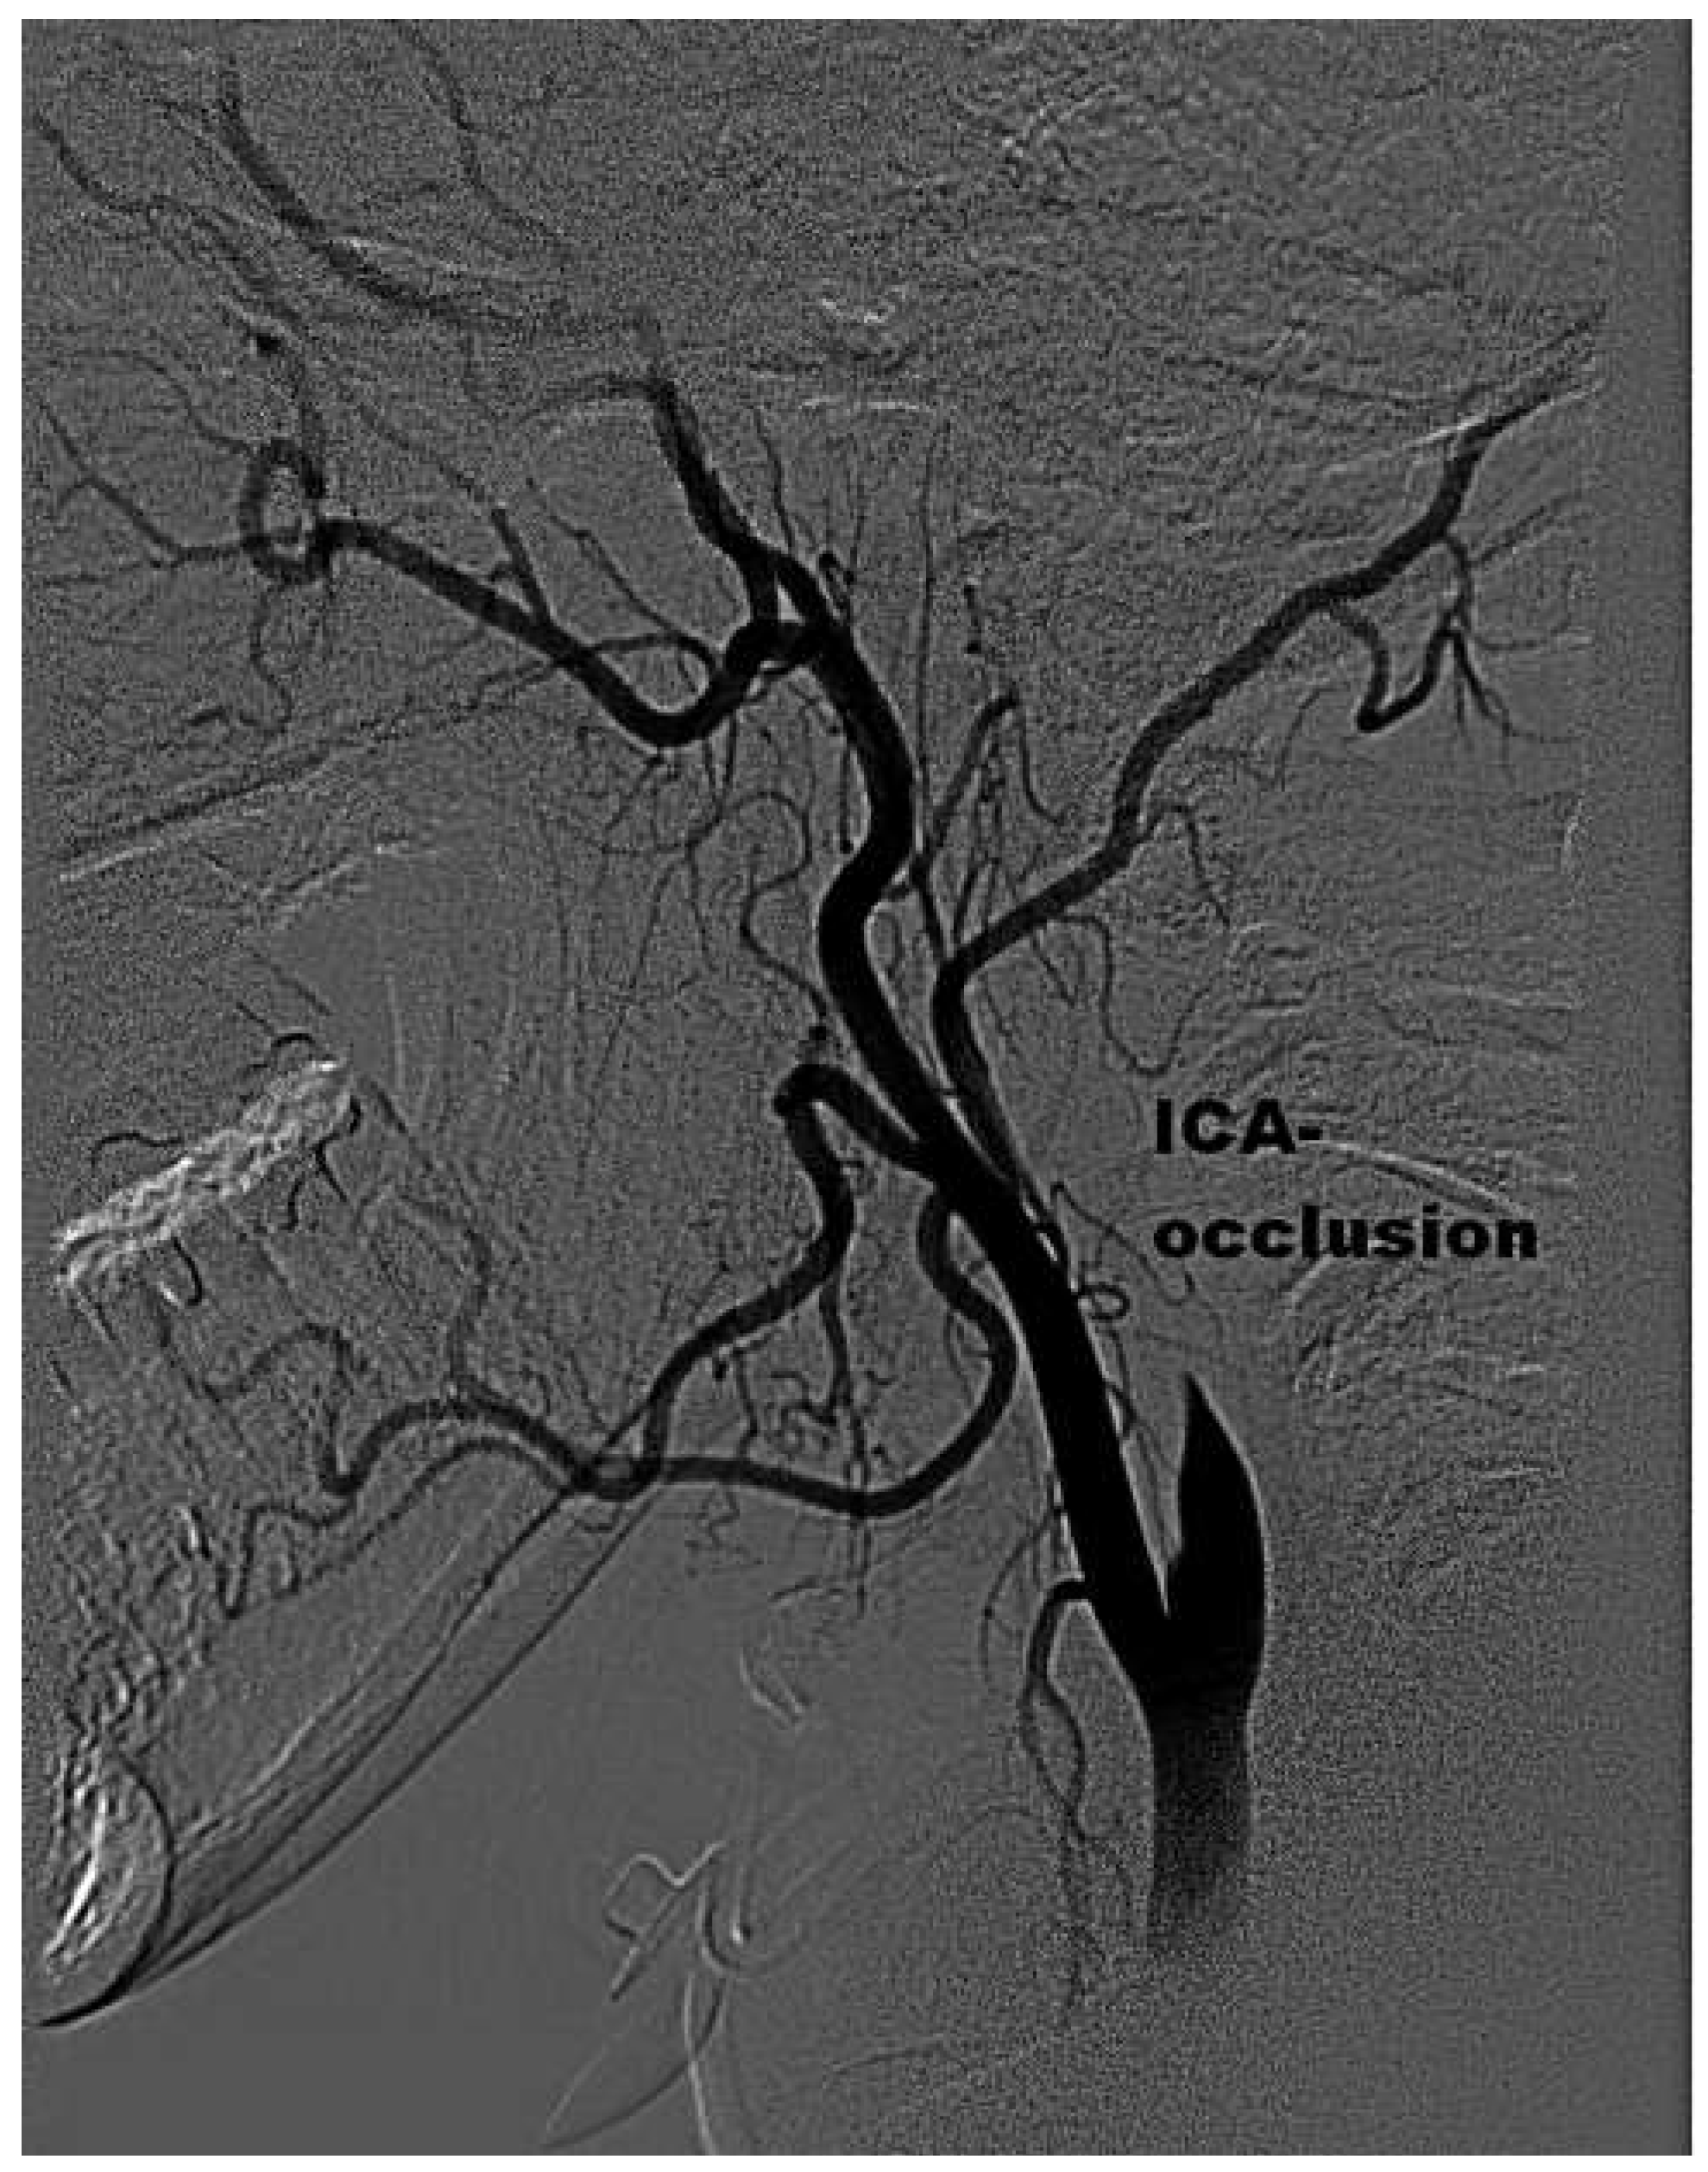

Mechanical Thrombectomy After Embolic Internal Carotid Artery Occlusion in Acute Stroke

Case presentation